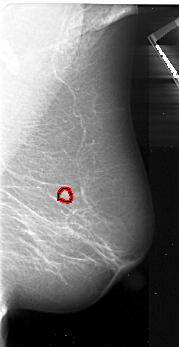

A_1048_1.RIGHT_CC

RIGHT_CC LINES 5026 PIXELS_PER_LINE 2506 BITS_PER_PIXEL 16 RESOLUTION 42 OVERLAY

FILE: A_1048_1.RIGHT_CC.OVERLAY

TOTAL_ABNORMALITIES 1

ABNORMALITY 1

LESION_TYPE MASS SHAPE IRREGULAR MARGINS ILL_DEFINED

ASSESSMENT 4

SUBTLETY 5

PATHOLOGY MALIGNANT

TOTAL_OUTLINES 1